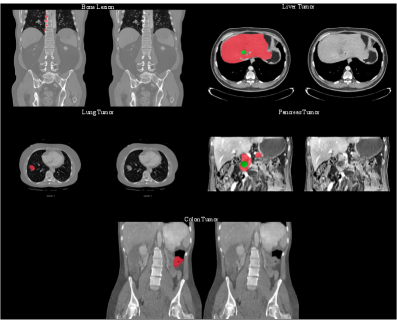

Refer to caption

Figure S3: The example of generated images from MAISI CT Generation task.

Figure S4: The example of generated images from MAISI Inpainting task.